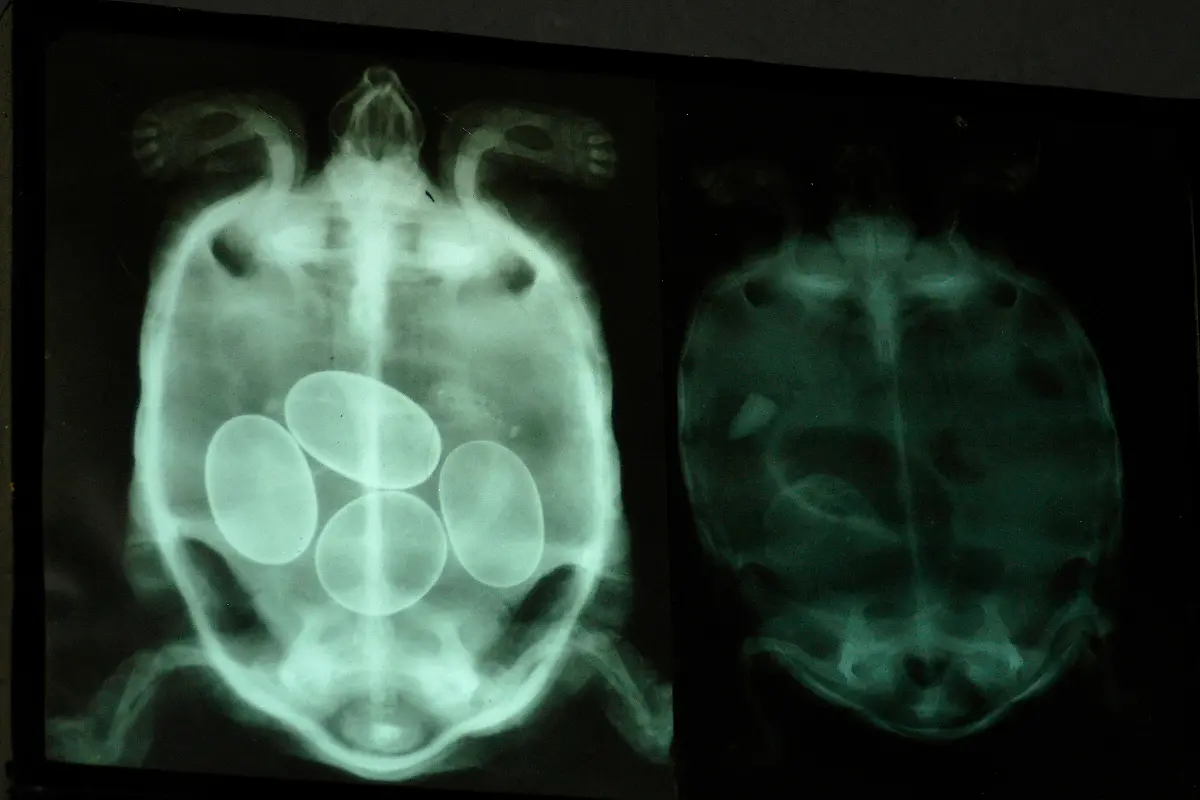

Nicht immer zeigen Röntgenaufnahmen das, was man von ihnen erwartet. Oft kommt es zu Bildern, die selbst hartgesottene Betrachter zum Schaudern bringen - und der Wissenschaft Rätsel aufgeben.